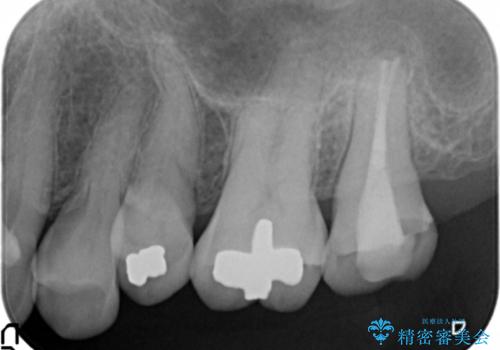

クラウンを装着した歯の虫歯の再発を防ぎ長い予後を期待するために削った箇所をしっかりとかぶせる適合の良さが必要はもちろんですが、セメントの漏洩を防ぐためにクラウンの十分な支台高径を歯周外科を行い獲得しました。

- インレーおよびクラウンは脱離するリスクがあります

- 形成量はセラミックより少ないですが、歯の形成、修復後に歯に症状が出ることがあります